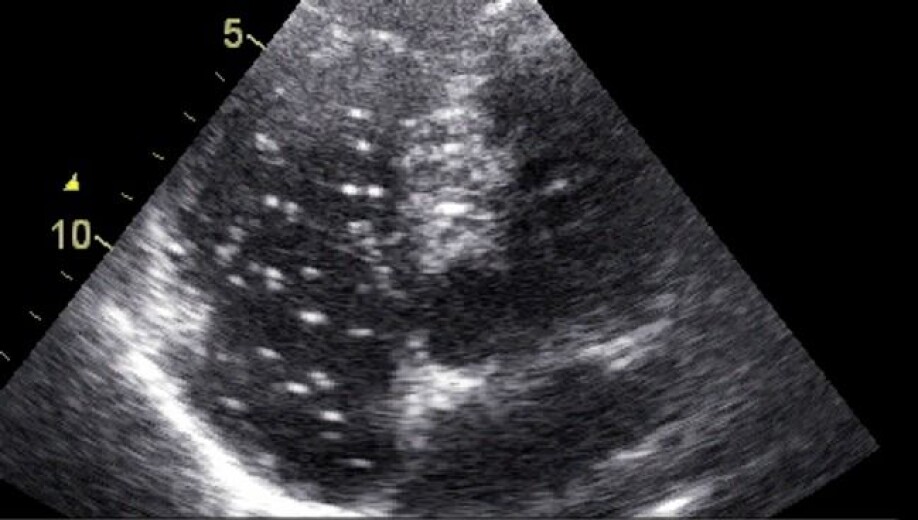

The researchers took the blood samples at two different times: within eight hours after the divers came out of the water and 48 hours afterwards, when the divers with DCS had undergone treatment in a pressure chamber. They performed RNA sequencing analysis to measure changes in the gene expression in white blood cells.